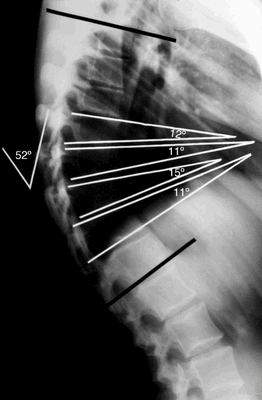

Рентгенограмма в боковой проекции

Согласно Sorenson, кифоз Шейермана характеризуется следующими критериями:

- Три или более соседних позвонков имеют клиновидную деформацию ≥ 5 градусов.

- Отсутствуют врожденные патологии позвоночника, а также его инфекционные заболевания и травмы.

Для оценки кифоза Шейермана необходимы тщательно собранный анамнез, физикальное обследование и рентгенограммы в боковой и передне-задней проекциях. Боковые рентгенограммы требуются при диагностике. Диагностическими критериями являются:

- Грубый гиперкифоз более чем 40 градусов.

- Передняя клиновидная деформация тела позвонка на 5 градусов или более (в трех или более соседних позвонках).

Также на рентгенограммах обнаруживаются:

- Неправильная форма у опорных площадок тел позвонков.

- Грыжи Шморля.

- Снижение высоты межпозвонкового пространства.

- Сколиоз.

- Спондилолиз / Спондилолистез.

- Грыжи дисков.